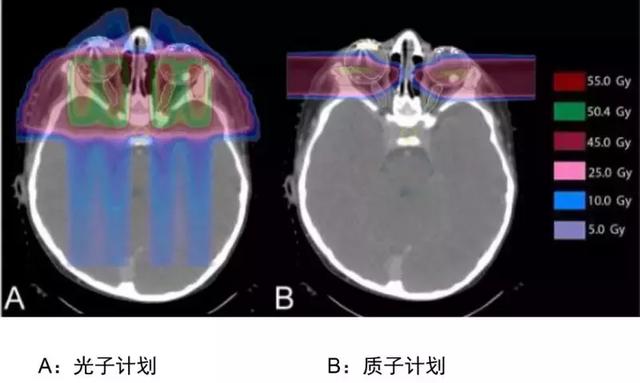

从剂量分布差异了解质子治疗的优势

解析:这是头颈部肿瘤剂量分布图比较,我们明显能看到两者的差异,常规放疗蓝色区域很大,说明射线对病灶周边的正常组织有不可避免的损害,质子放疗可以减少咽喉和口腔部位的放疗损伤,降低发生口角炎、口腔炎、吞咽困难、口干的发生率。